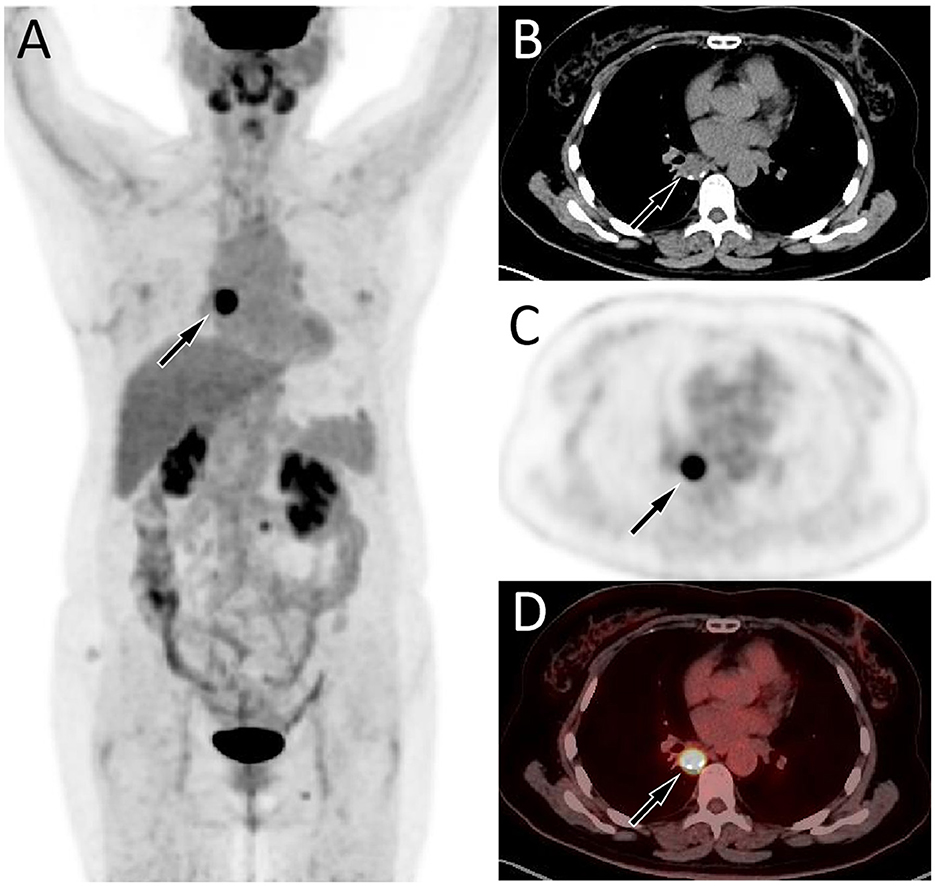

A 57-year-old female patient accidentally discovered a soft tissue mass in her posterior mediastinum during a physical examination in an outside hospital on 11 November 2023. She consciously had no obvious clinical symptoms and was not paid attention to, nor was undergoing any treatment. On 20 April 2024, the patient came to our hospital for medical help due to a cough and chest tightness. The physical examination did not reveal any positive signs. She and her family have denied any history of cancer or major genetic disorders. The serological laboratory test results revealed that the treponema pallidum antibody was positive, while other results, including blood routine, liver and kidney function, and serum tumor markers, were all negative. She had a history of syphilis 15 years ago; the condition resolved completely following treatment, and there are currently no clinical or serological indications of recurrence. She denied any history of tuberculosis, hepatitis, or malignancies. The patient underwent chest computed tomography (CT) examination (Figure 1) on April 24, which revealed a well-defined soft-tissue density mass in the posterior mediastinum with calcification. Contrast-enhanced CT showed a slight enhancement of the mass, suggesting a possible neurogenic tumor. The patient underwent surgical complete resection of the tumor through thoracoscopy under general anesthesia on April 26 after completing the preoperative routine examination. During the operation, the tumor was found to be located between the spine, azygos vein, trachea, and esophagus, with a size of approximately 6 cm × 4.5 cm × 4.0 cm, spindle-shaped, with a complete capsule and no obvious adhesion to surrounding structures. The tumor was gradually separated along its edges using an ultrasonic knife until it was completely removed, and then sent for pathological examination. Hematoxylin–eosin staining (as shown in Figure 2) showed that the excised tumor tissue appeared as a gray–red envelope block with intact capsule, medium texture, and calcified lesions in some areas. No tumor invasion was observed at the resection margin. Immunohistochemistry revealed tumor cells positively expressed vimentin, Cluster of Differentiation 34 (CD34), cytokeratin (CK), and CD56, while they negatively expressed insulinoma-associated protein 1 (INSM1), S100, CD68, and so on. Based on these histopathological findings of the patient, she was diagnosed with PES. After surgery, the patient did not receive further radiotherapy, chemotherapy, or other treatment methods. At 4 months after discharge, a chest CT examination revealed a new soft tissue density nodule at the site of her previous surgery. In order to further evaluate the nature of the nodule and determine the next treatment plan, the patient underwent 18F-FDG PET/CT imaging (as shown in Figure 3) on August 20. The results showed that the above nodule, as shown on CT, showed a significantly increased 18F-fluorodeoxyglucose (18F-FDG) uptake, while no significant hot spots were observed in the rest of the body. These imaging findings suggested the possibility of local recurrence of the tumor, and due to the limitation of the lesion, the surgeon planned to perform a second operation on her. However, the patient refused surgery again. On October 16, the patient returned to the hospital for chest pain and underwent chest CT examination (Figure 4), which showed that the mass was significantly larger than before. Currently, she is receiving a chemotherapy regimen of epirubicin in combination with isocyclophosphamide.

Figure 4

The patient's chest CT 6 months after surgery, CT plain scan (A) and contrast-enhanced CT (B) revealed a significant increase in the volume of the mass, with a maximum cross-sectional area of about 4.7 cm × 3.9 cm.